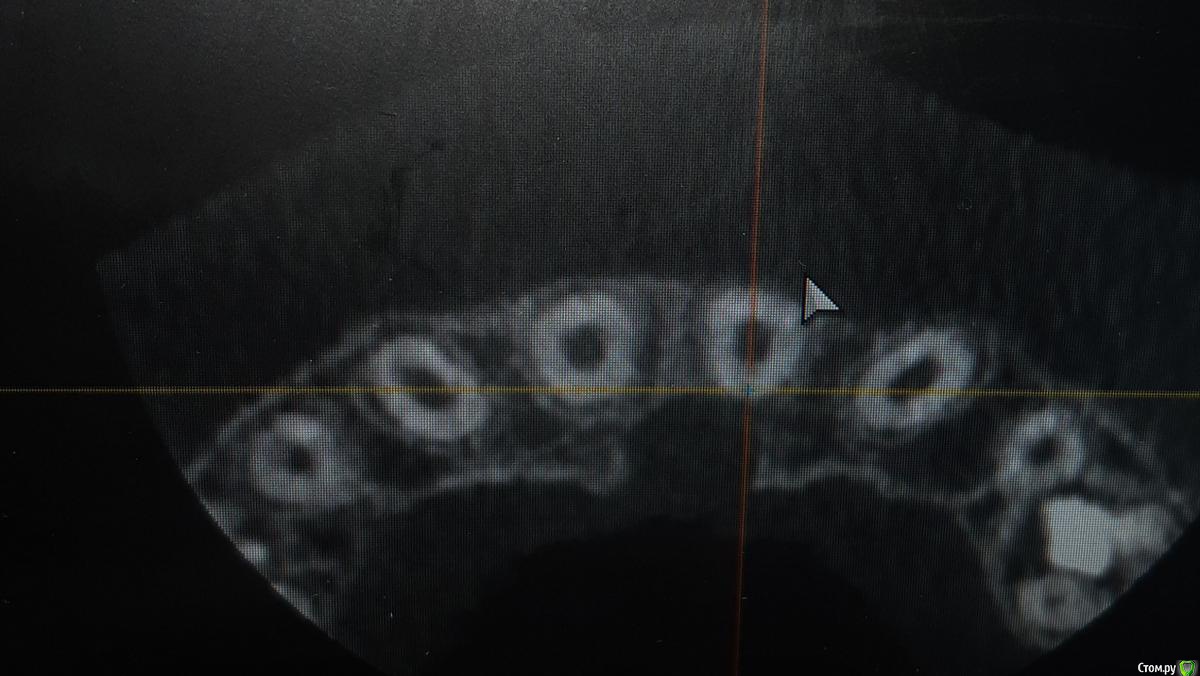

ANCHOUSE Опубликовано 30 марта, 2019 Автор Поделиться Опубликовано 30 марта, 2019 Сделали ктhttps://yadi.sk/d/W9n5FOqj7Rpb4A Ссылка на комментарий

ANCHOUSE Опубликовано 30 марта, 2019 Автор Поделиться Опубликовано 30 марта, 2019 Почему нет кортикалки между 21 и резцовым каналом? Ссылка на комментарий

kramer Опубликовано 30 марта, 2019 Поделиться Опубликовано 30 марта, 2019 Мне кажется, кость рассосалась вследствие возникновения этого новообразования. 1 Ссылка на комментарий

ANCHOUSE Опубликовано 30 марта, 2019 Автор Поделиться Опубликовано 30 марта, 2019 Или от постоянной нагрузки? Ссылка на комментарий

ANCHOUSE Опубликовано 30 марта, 2019 Автор Поделиться Опубликовано 30 марта, 2019 Что имеете ввиду?Сам факт травмы, как раз на эту область Ссылка на комментарий